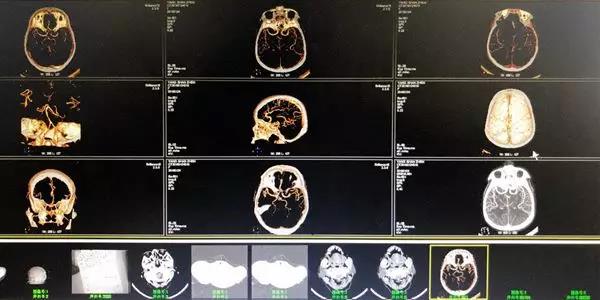

静脉溶栓后复查cta,血管显示清晰。